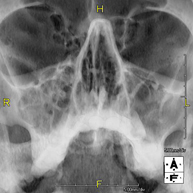

- RX Senos Paranasales

Técnica mediante la cual, utilizando rayos X, se obtienen imágenes de los senos paranasales para su estudio. Indicaciones: dificultad respiratoria nasal, tos crónica, cefalea, mucosidad.

Técnica mediante la cual, utilizando rayos X, se obtienen imágenes de los senos paranasales para su estudio. Indicaciones: cefalea, tos crónica.